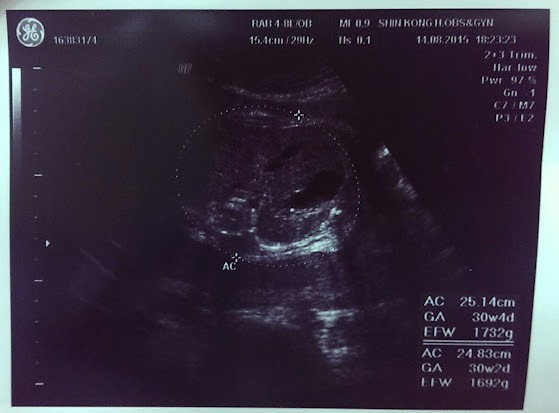

產檢日期:8/14(33W+1)

經歷了3周前的安胎洗禮後,雖然小瑰用牛肉來補毛毛,但是她好像挺不賞臉的,只從1435g增加到1732g,讓小瑰無所適從,因為全部的人都一直說~吃牛肉、吃牛肉,但顯然我家毛毛嘸~甲~意~